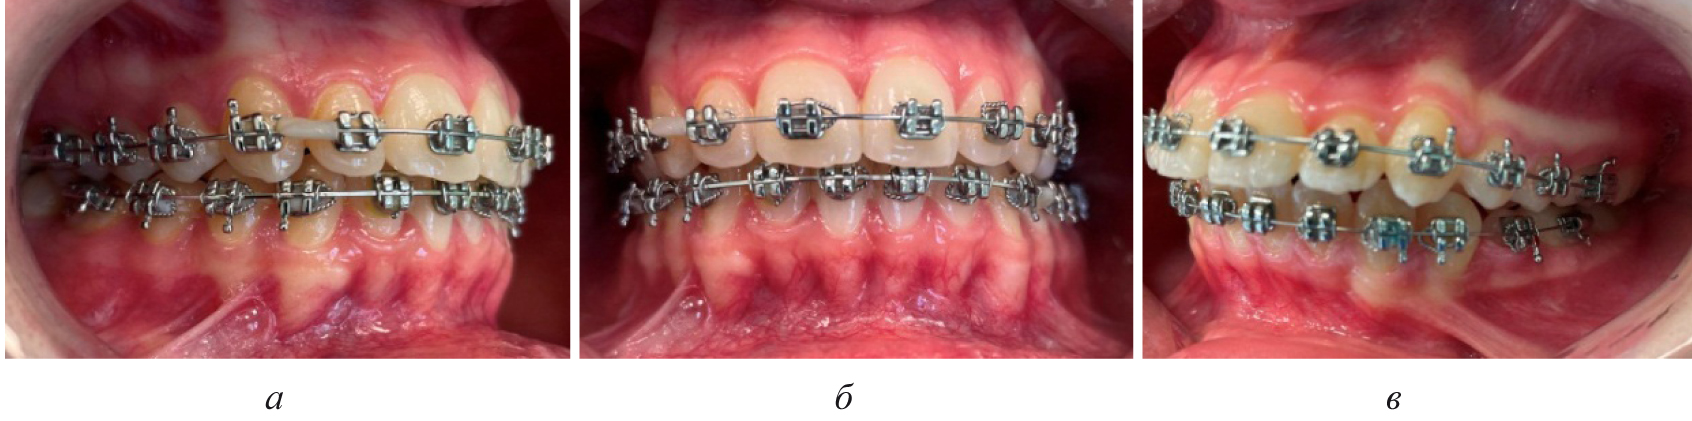

Лечение пациентов, как правило, проводилось с использованием несъемной ортодонтической аппаратуры, в частности эджуайс-механикой.

На первом этапе проводилось раскрытие пространства в области ретенированного зуба и создания условий для его прорезывания. После этого устанавливались элементы аппарата на противоположной челюсти (рис. 4).

Последующие этапы ортодонтического лечения техникой эджуайс проводились с учетом общепринятого протокола и этапности смены металлических дуг, что способствовало нормализации окклюзионных взаимоотношений (рис. 5).

Рис. 4. Создано место для прорезывания премоляра (а), установлена аппаратура на верхнюю челюсть (б)

Рис. 5. Окклюзионные взаимоотношения справа (а), спереди (б) и слева (в) на завершающем этапе лечения